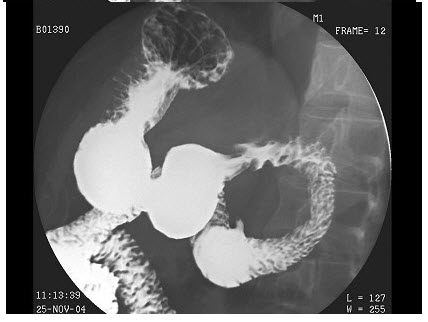

B.不规则腔内充盈缺损

C.管壁僵直,蠕动消失

D.纵隔内软组织肿块

E.恶性溃疡龛影

19、单项选择题

男,55岁,中上腹隐痛多年,剑突下压痛,影像检查如图,最可能的诊断是()